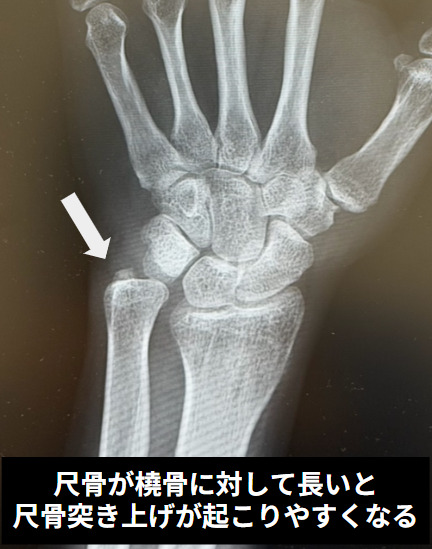

とくに大きな要因は、尺骨が相対的に長い状態(「尺骨プラス変異」といいます)です。尺骨が長いほど、小指側の関節に体重や力が集中しやすくなり、痛みや変性が起こりやすくなります。また、手首の骨の傾き(橈骨の角度)が変わることでも、小指側にかかる負担が増える場合があります。

画像検査では、まずレントゲン(単純X線)で、尺骨が相対的に長いかどうか(尺骨プラス変異)を確認します。さらに、月状骨や三角骨といった手首の骨に、骨の中が少し抜けたように見える所見(骨嚢腫のような変化)がみられることがあります。